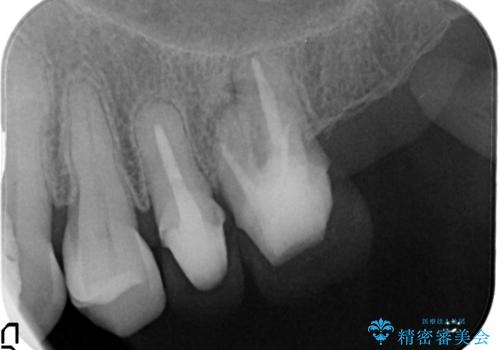

左側の上下の奥歯に適合が悪く、レントゲン上でも根の治療が必要なところがありました。

再治療を行いました。

根管治療からの再治療を行ったことにより、治療期間が多少長くなりましたが、今後再治療の必要性があまりないような、精度の高い治療ができました。